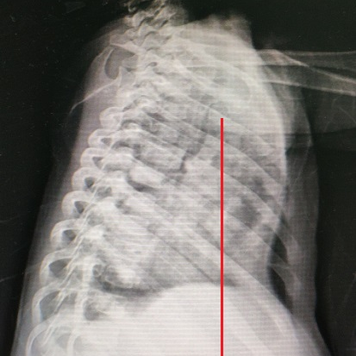

Shortly after birth, the child was diagnosed with pectus excavatum, manifested as a sunken anterior chest wall. This condition often causes breathing difficulties and even severe paradoxical breathing. Additionally, the child has suffered multiple episodes of severe pneumonia, leading to several hospitalizations without full recovery. Given the severity of the chest wall deformity and its complications, the parents are eager for early surgical treatment.

The mid-lower part of the anterior chest wall exhibits a noticeable depression, accompanied by significant paradoxical breathing. Moreover, heart pulsations in the anterior chest wall and a protruded costal arch are evident. The patient was diagnosed with severe pectus excavatum, which had caused significant compression of the heart and lungs.

The surgery, lasting only 9 minutes and 48 seconds, utilized the standard Wang procedure to correct the chest wall deformity. After the surgery, the deformity was resolved, restoring the chest wall to its normal shape and eliminating the symptoms of pardoxical breathing.